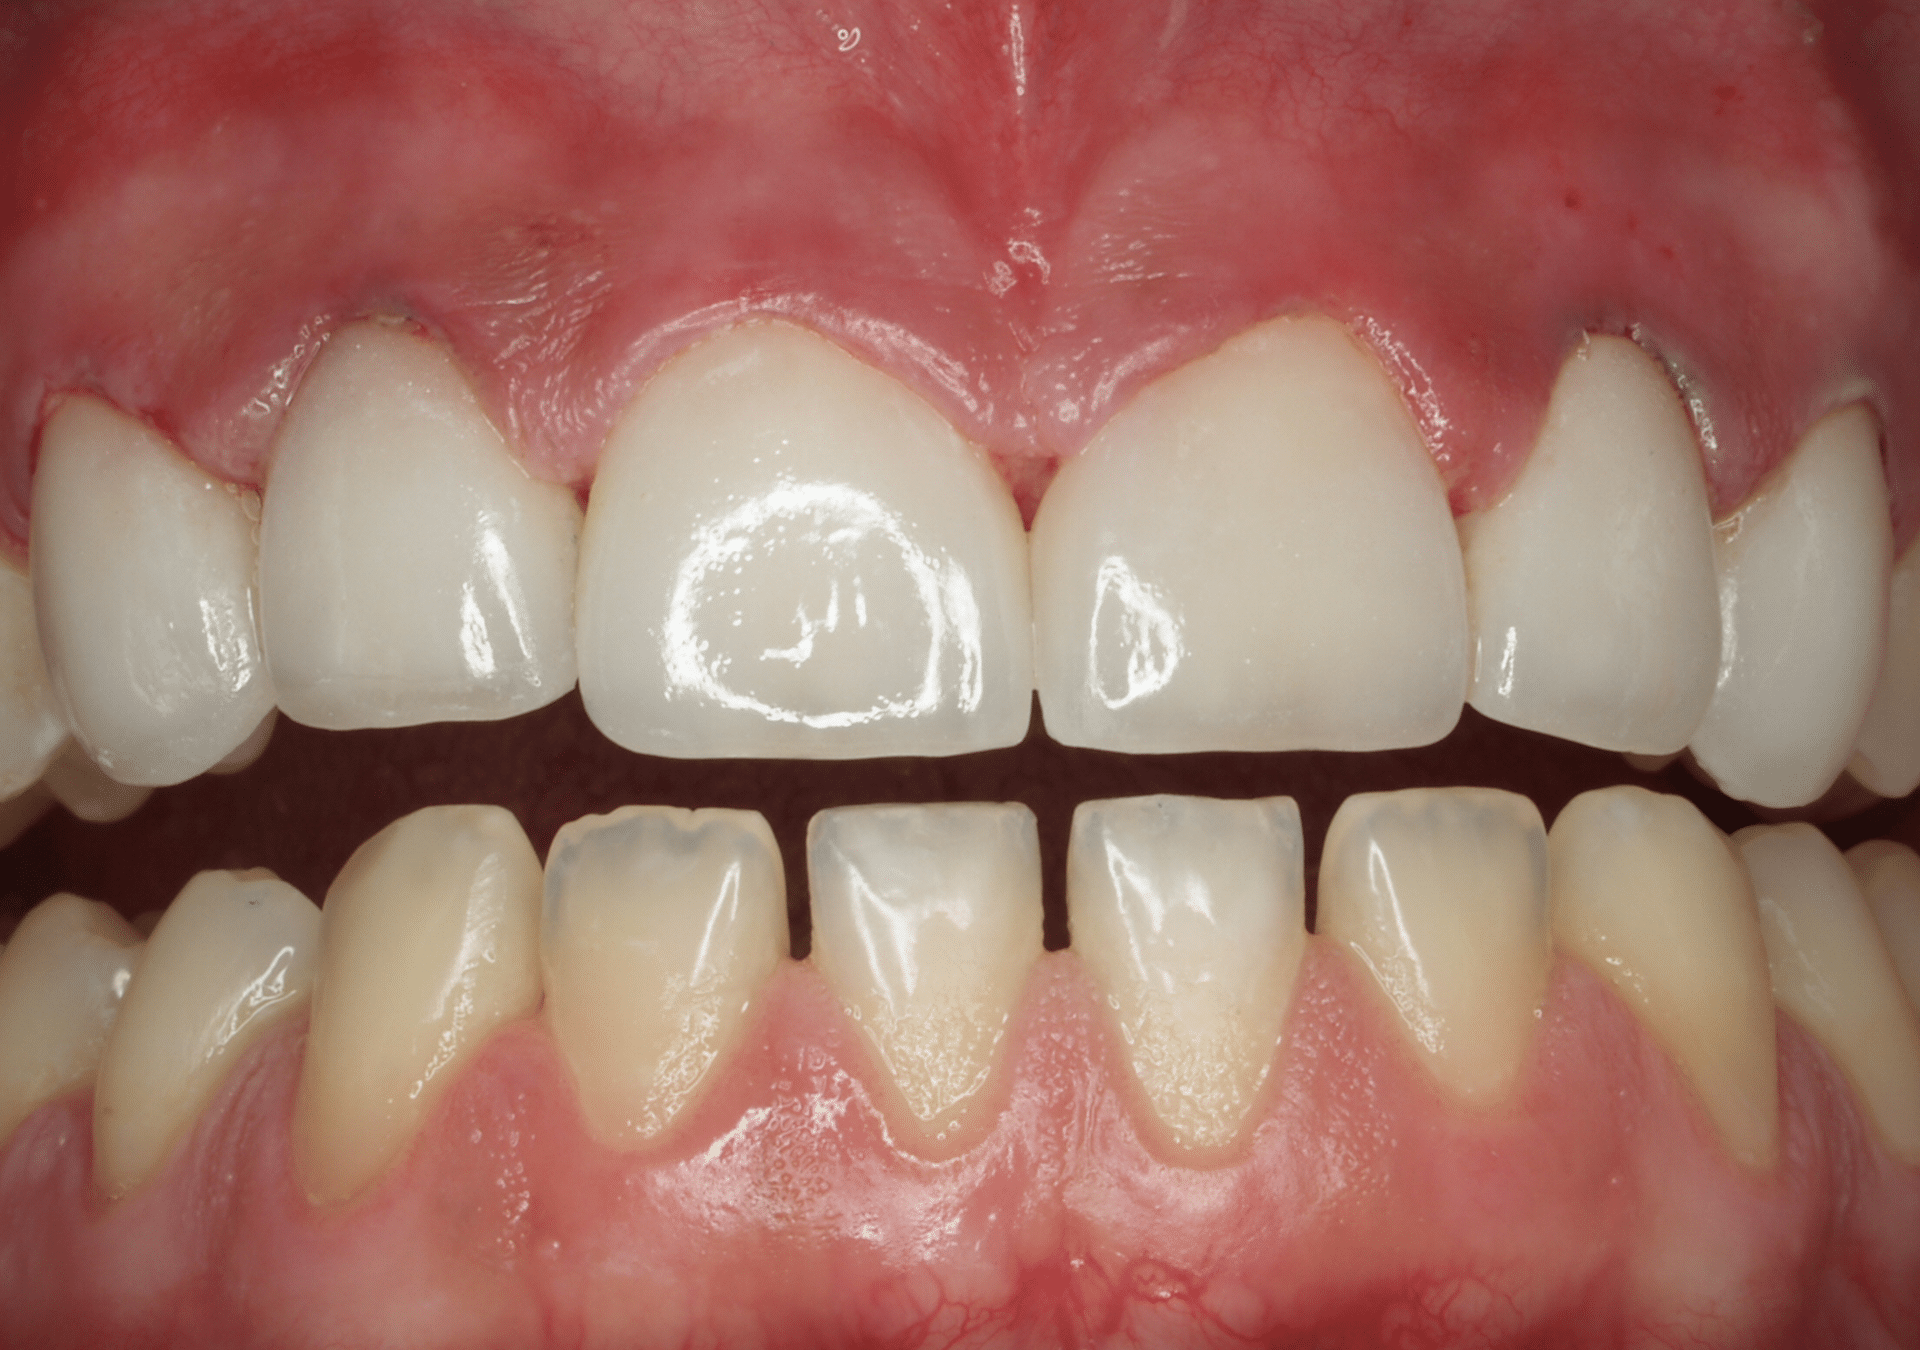

Caso 1

Carillas de cerámica feldespática superiores e inferiores con cierre de diastemas.